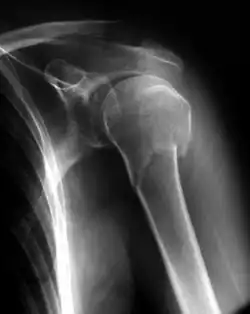

Fracturas proximales del húmero

Al extremo superior del húmero se le conoce como epífisis proximal y es una región que se fractura con poca frecuencia y cuando ocurren, es principalmente en personas mayores de 60 años.[3] El tratamiento suele ser conservador con manejo del dolor e inmovilización con férula y posterior rehabilitación con fisioterapia. La verdadera incidencia de desgarros del manguito rotador es desconocida. Son más comunes en pacientes de mayor edad, las lesiones de alta energía, y donde existe un importante desplazamiento.